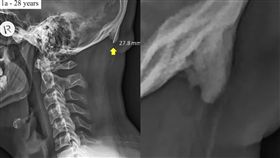

長期低頭玩手機!小心頭骨後方長骨刺

科技的進步改變人類生活方式,不過也帶來許多文明病,近...